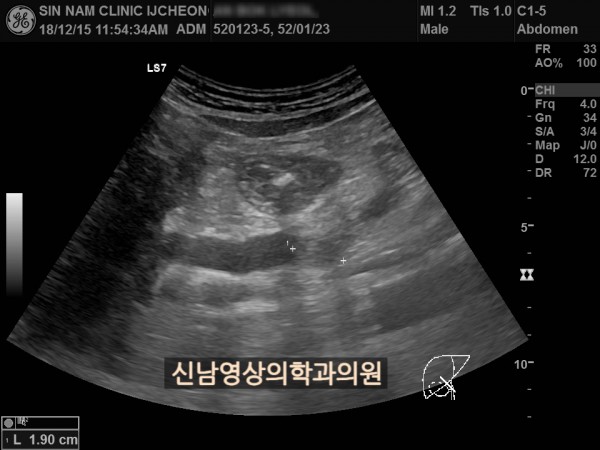

상복부 초음파 적용 사례

본 환자분은 50대 중반의 남성분으로 손가락안이 가렵다는 느낌으로 내원하셨습니다.

담도암과 담관암은 같은 질환을 지칭하는 용어로 간에서 만들어진 담즙이 십이지장으로 이동하는 통로인 담관에 발생하는 악성 종양입니다.

이 암은 간 안에 생기는 간내 담관암과 간 바깥에 생기는 간외 담관암으로 나뉘며, 가장 흔한 증상으로 통증이 없는 황달, 짙은 소변, 옅은 변, 복통, 체중 감소, 소양증 등이 나타날 수 있습니다.

치료는 암의 위치와 진행 정도에 따라 수술, 항암 치료, 담관 스텐트 삽입 등으로 이루어집니다.